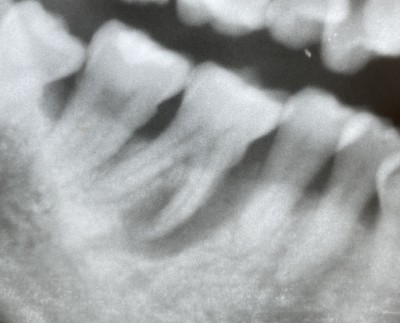

【下顎大臼歯根管治療】